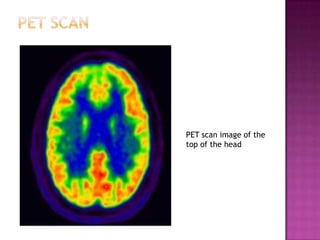

Neuroscientists use four main methods to measure brain activity and correlate it with behavior: 1) examining brain anatomy using CT or MRI scans; 2) recording brain activity during tasks using EEG, MEG, PET, or fMRI scans; 3) studying the effects of brain damage; and 4) examining the effects of stimulating specific brain areas using transcranial magnetic stimulation or injecting chemicals. However, interpreting the results of brain stimulation experiments is challenging because behaviors involve multiple brain regions.